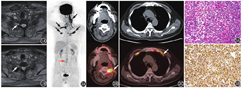

患者男,58岁,3个月前无诱因出现颈痛、右上肢尺侧疼痛麻木,进行性加重,手握力减弱。以颈椎病收入院。入院体格检查:颈椎生理性前凸减小、侧屈、前屈及后伸活动受限,颈椎下部各棘突及棘旁压痛、叩击痛和放射痛。右上肢前臂及右手尺侧感觉减退。实验室检查:血尿常规、肿瘤标志物均未见异常。颈椎病术前MR平扫(图1)示颈7~胸1节段右侧神经根增粗,T2加权成像(weighted imaging, WI)信号略高。入院后患者因进行性双上肢无力、疼痛加重行18F-FDG PET/CT显像。静脉注射18F-FDG 240 MBq(本科日本住友株式会社HM-12回旋加速器生产,放化纯>95%)后60 min行PET/CT显像(东软医疗系统股份有限公司NeuWise PET/CT仪),结果(图2)示:颈胸部椎管两侧颈丛、臂丛、双侧第1~2肋间胸神经前支走行区多处线状、放射状、结节状分布高代谢灶,SUVmax 8.2~14.2,腰1~4椎管内条形稍高代谢灶,SUVmax 3.2;余未见异常高代谢灶。上述改变高度倾向原发性周围神经淋巴瘤病(neurolymphomatosis, NL)。

左侧胸壁神经穿刺活组织检查(简称活检)病理结果(图3A)示:穿刺组织内见淋巴样细胞弥漫浸润,细胞体积大,见小核仁,核分裂象和吞噬现象易见;免疫组织化学染色结果(图3B)示病灶CD20、B细胞淋巴瘤(B cell lymphoma, Bcl)-2基因及Bcl-6基因均呈阳性表达,诊断为非霍奇金弥漫性大B细胞淋巴瘤(diffuse large B cell lymphoma, DLBCL)。患者行2个疗程常规方案化疗后,症状明显好转,但在行PET/CT疗效评估前、化疗间歇休息期因急性肺栓塞死亡。